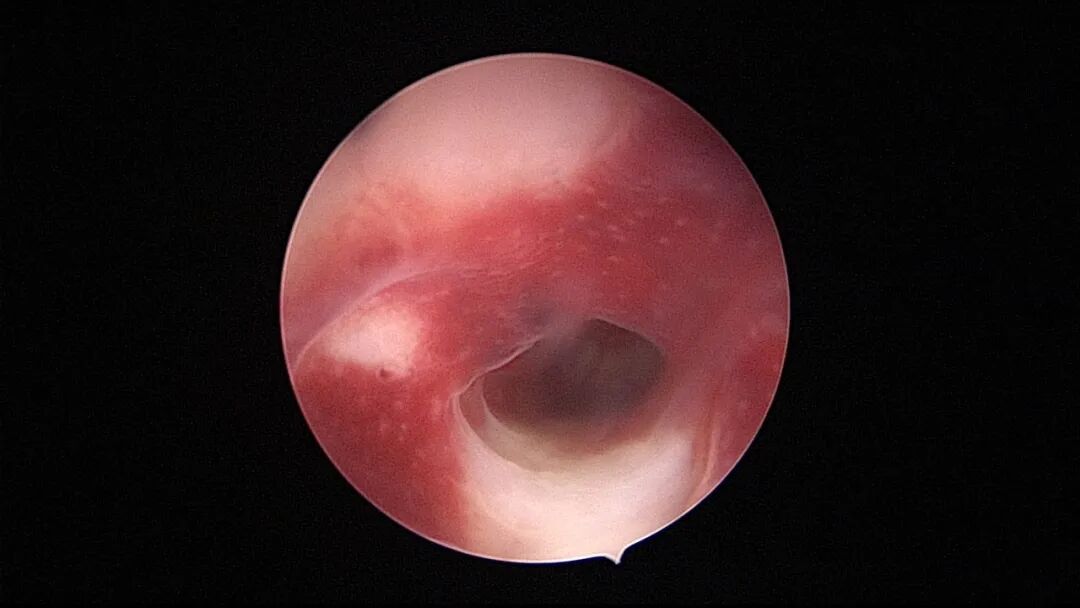

第三次宫腔镜:2021年9月,停经1+月,排除带环受孕,门诊B超提示宫腔粘连,节育环嵌顿。宫腔镜探查见γ型环嵌顿,宫腔广泛粘连,异物钳取环,环变形。单极电针分粘,恢复宫腔形态,显露双侧输卵管开口,右侧输卵管开口周围及宫底部分内膜正常,左侧宫角周围内膜薄,宫腔中部前后壁粘连创面集中,宫腔灌注生长激素。